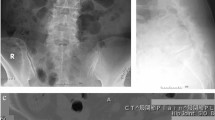

Based on computed tomography (CT) images, facet joint arthropathy of the lumbar spine was graded using a 4-grade scale as proposed by Weishaupt et al.22 Weishaupt’s classification of facet joint degeneration has been extensively used23,24. Two orthopaedic spine surgeons (P–H. C. and Y-C. Y. with 10-year and 5-years clinical experiences, respectively), who were not involved in the surgical treatment of included patients, graded the severity of facet joint arthropathy independently; disagreements over grading were resolved by consensus. Example CT images for 4 grades of facet joint arthropathy are shown in Fig. 1. We examined 5 facet joint levels, including L1-L2, L2-L3, L3-L4, L4-L5, and L5-S1. Since each level has 2 sides (right and left), each patient had 10 numerical grades of facet joint arthropathy.